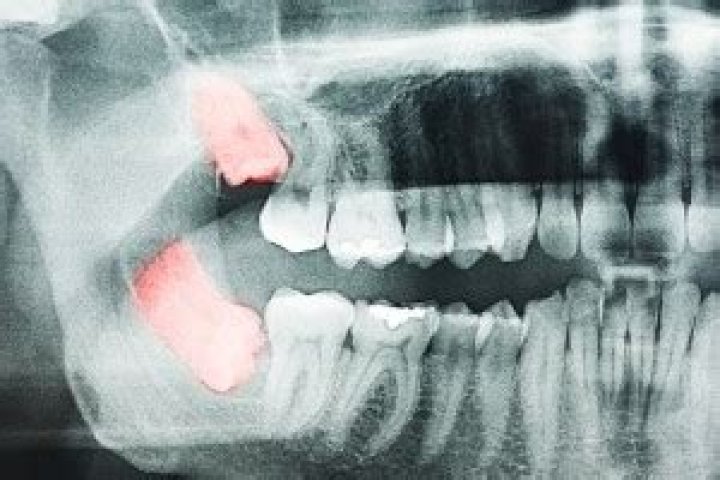

A wisdom tooth abscess is considered a dental emergency, and you should seek immediate treatment if you present with the symptoms of a dental abscess anywhere in your mouth. It is not uncommon for an abscess to develop as a result of impacted wisdom teeth.

Signs and symptoms of a tooth abscess include: Severe, persistent, throbbing toothache that can radiate to the jawbone, neck or ear. Sensitivity to hot and cold temperatures. Sensitivity to the pressure of chewing or biting.

1. Open up (incise) and drain the abscess. The dentist will make a small cut into the abscess, allowing the pus to drain out, and then wash the area with salt water (saline).